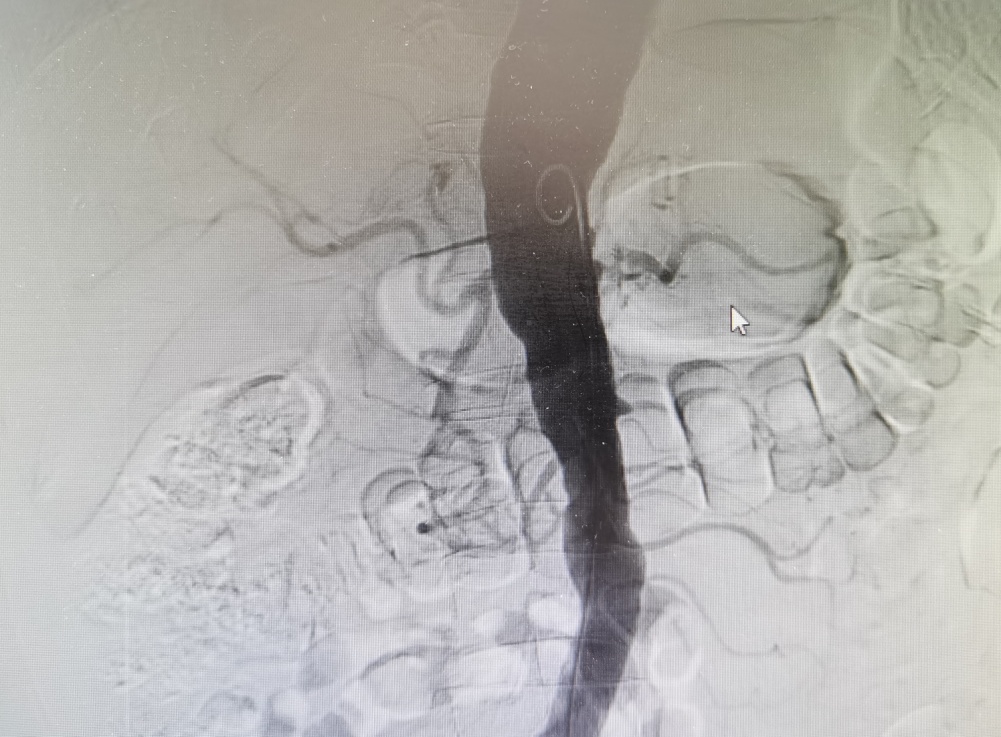

待冷大叔生命体征平稳后,柳海华主任医师立即行肾动脉造影检查,在造影过程中发现其左侧肾动脉主干完全闭塞,右侧肾动脉起始部狭窄95%。“也就是说冷大叔的全部肾功能仅靠那微弱的5%的血流挣扎,随时都有肾梗死的可能。”袁东介绍,在与家属积极沟通后,立即为患者实施右侧肾动脉支架植入术。

双侧肾动脉几乎不显影